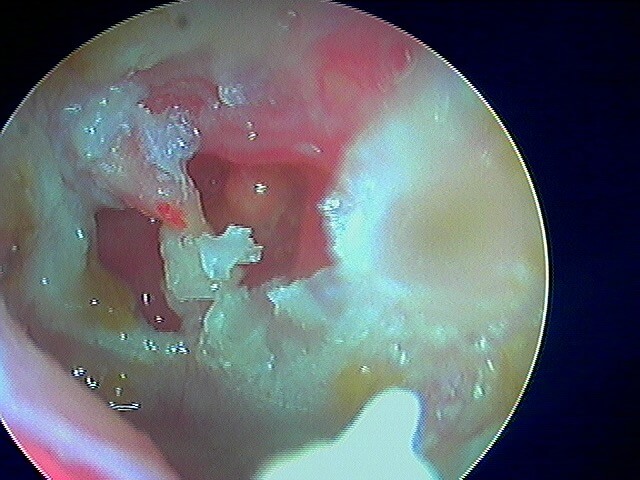

2/6 cholestéatome du CAE

Rare le cholestéatome du CAE, le tympan étant normal. Le diagnostic otoscopique est posé par la présence de squames et d'érosion osseuse. Ce sont des patients qui font des otites externes très rapprochées.

Post-opératoire à 1 an (le cadre osseux s'est reconstitué seul, j'avais juste fraisé):

Post-opératoire à 2 ans:

Post-opératoire à 3 ans: